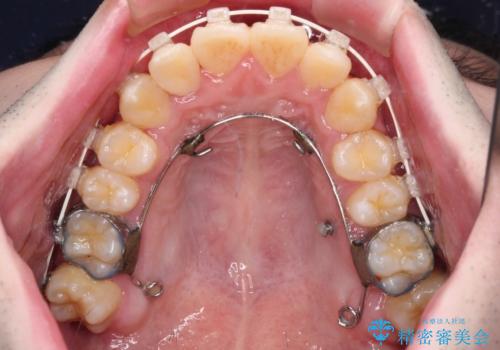

全顎的なクロスバイト 補助装置を用いてワイヤー矯正

前歯のクロスバイトや八重歯の他に、左右最後臼歯のシザーズバイト(鋏状咬合)が認められました。

シザーズバイト改善のために補助装置を使用しながら、ワイヤー装置にて全体の歯列を整えることとしました。

シザーズバイトは強く咬合する奥歯を移動させるため、多くの場合においてワイヤー矯正の装置のみでは改善が困難となります。

奥歯の咬み合わせ改善は治療初期からしっかりとアプローチする必要があるため、補助装置を積極的に利用します。